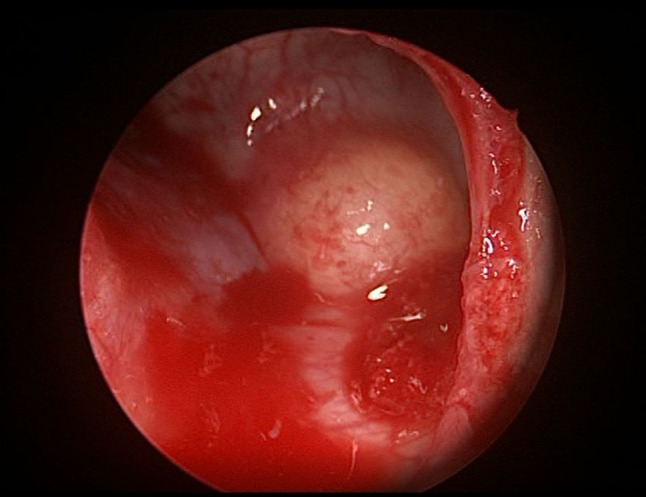

Fig. 1.

Tran-antral endoscopic view of odontogenic maxillary cyst